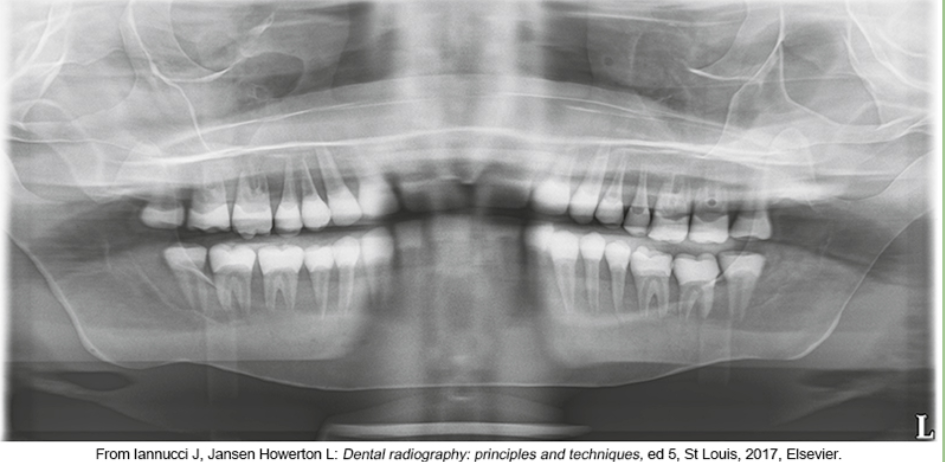

whats the problem

chin too low